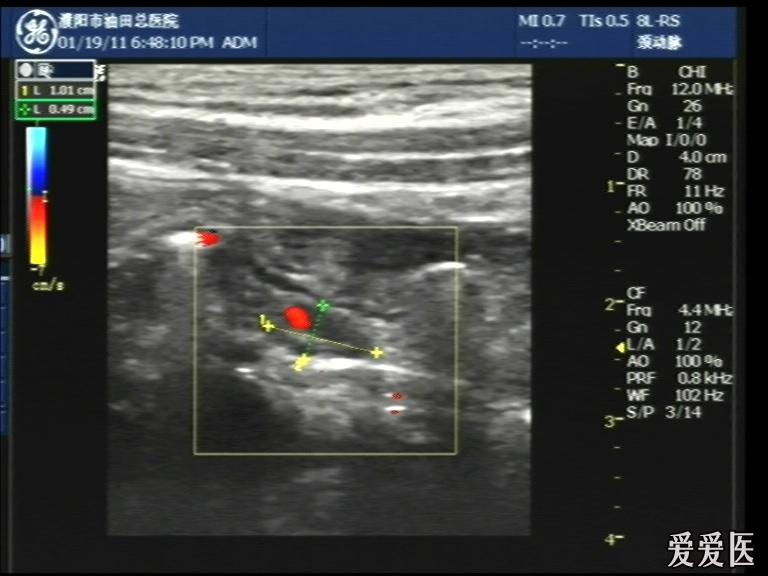

超声检查:于下腹部可见“双环征象”,双环重叠长约6mm,检查期间观察可见肠蠕动;CDFI:未见明显异常血流信号。

超声提示:下腹部双环征,考虑肠套叠可能,请结合临床